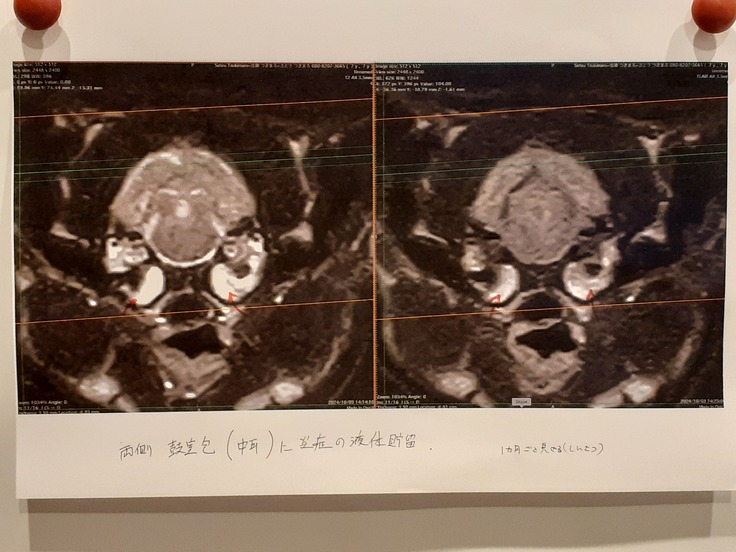

大脳低形成もそうですが、更にMRIにて両側鼓室包に炎症の液体がたくさん貯まっていることがわかりました。

いわゆる酷い中耳炎です。

説明を聞くと中耳炎の方がかなり重症だなと感じました。

今後の治療方針としてはまず3か月の抗生剤治療。

排出されたかの判断は3か月後のCT検査

それにより治っていなかったらそれこそ大変な手術で骨を貫き、脳に繋がる神経、血管を避けながら管を入れ1週間入院しながら液体を抜くというものです。

とても慎重な技術ということで失敗すると涙腺が塞がったり、顔が変形したり麻痺もあるそうです。

ですがまずは抗生剤治療を3か月しながら酷くなってしまった場合の変化を見逃さず観察、変化があったら即CTになります。変わらなければ1か月ごとの診察になります。